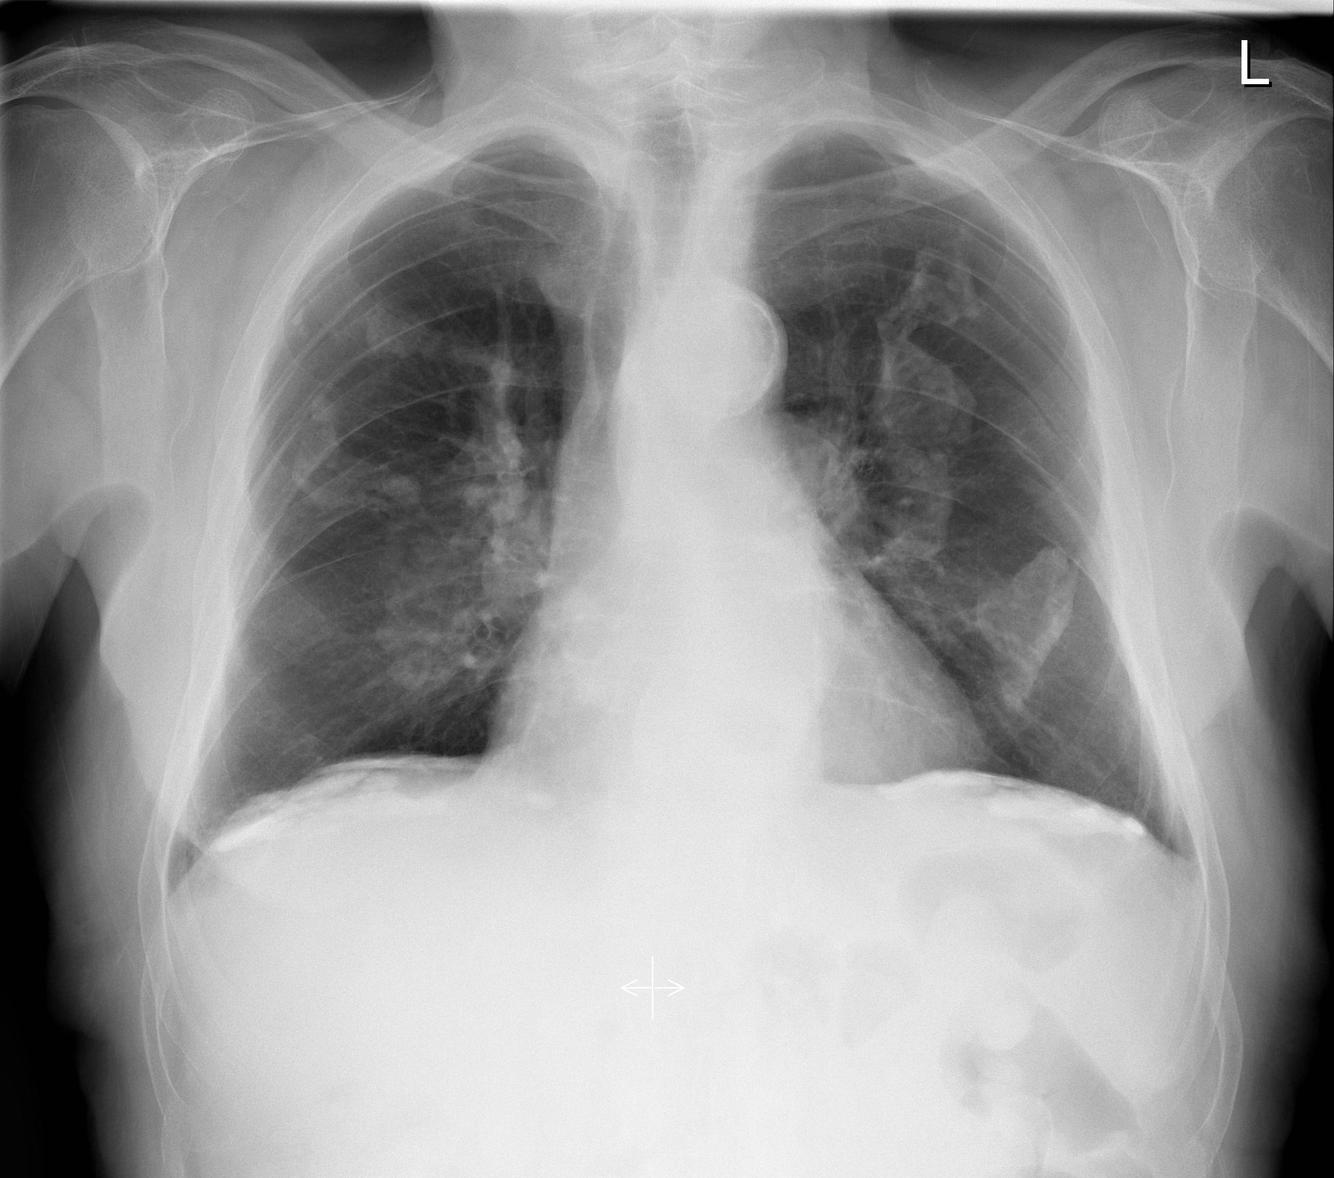

BHL

Sarcoidosis, malignancy, TB

Ask about joint pain, cough